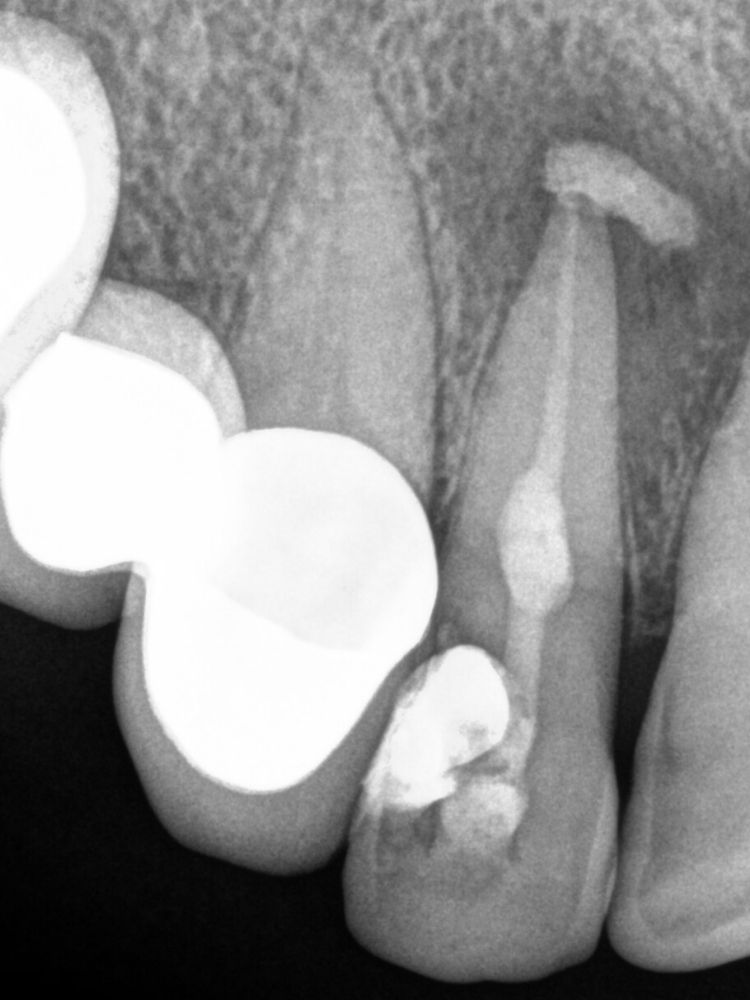

En una segunda cita pasamos al siguiente peldaño del tratamiento. Procedimos a retirar todos los materiales intraconducto y obturar. Para ello, en primer lugar, se realiza el Downpack con System B para sellar el tercio apical. A continuación, con la técnica de inyección de gutapercha, se rellena el tercio medio y coronal del conducto de la pieza 1.2, con el consiguiente sellado de la cavidad de la reabsorción.

Para el éxito de este tratamiento de endodoncia con reabsorción interna es fundamental el uso de la gutapercha termoplástica. Con ello, somos capaces de obturar. Un ejemplo de cómo, pese a no tener en su historial unos antecedentes marcados que pudieran hacer prever este problema, unas molestias y las revisiones periódicas pueden ayudar a detectar una problemática a tiempo de resolverla antes de que vaya a más.